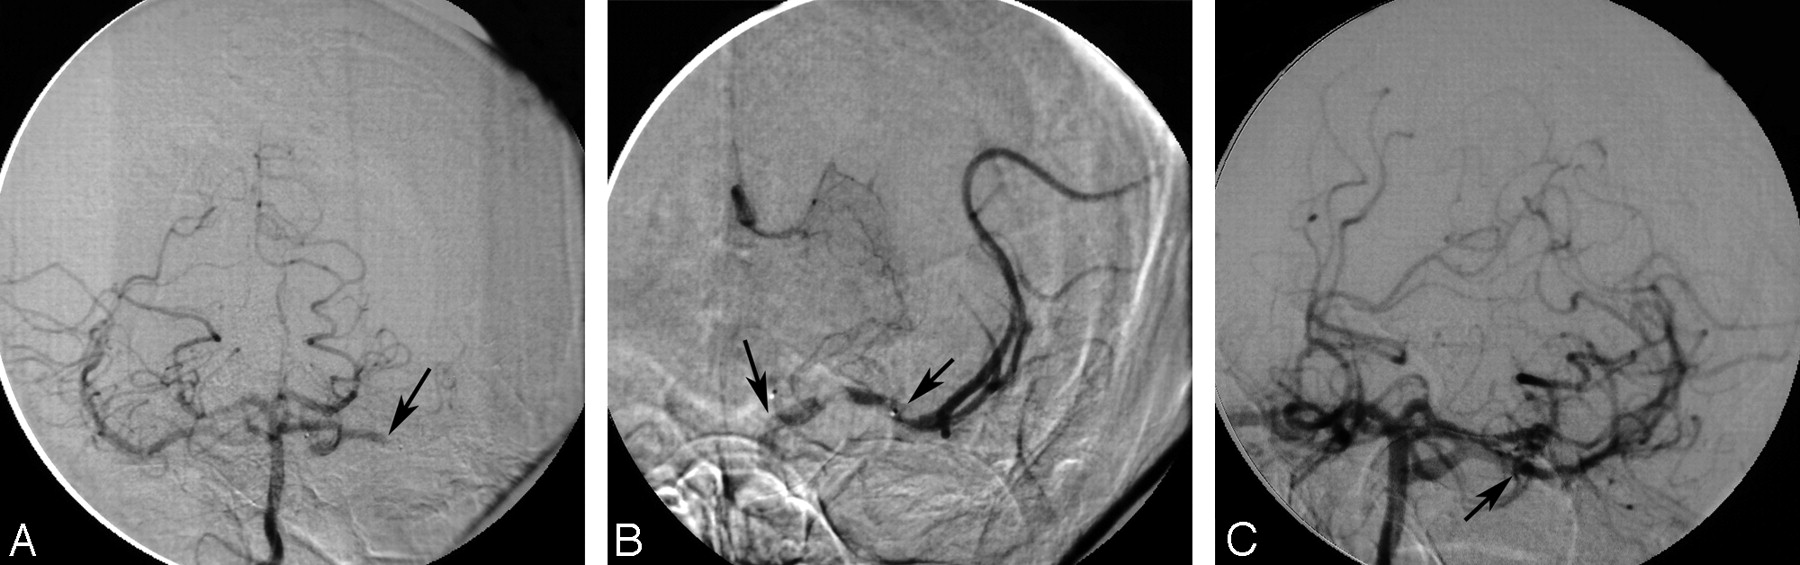

An arteriogram of the left common carotid artery revealed complete occlusion of the left ICA in the neck (Case 3 in Tables). There was no filling of the MCA territory. The right common carotid artery arteriogram demonstrated a complete occlusion of the right ICA in the neck. An arteriogram of the right vertebral artery showed bilateral filling of the posterior communicating arteries supplying both distal ICAs. The left M1 segment of the MCA was occluded (Fig 1A). A 6F guiding catheter was placed in the right vertebral artery. A Micro-Softstream (Boston Scientific, Natick, Mass) microcatheter was advanced (over a 0.014-inch microguidewire) into the basilar artery, then forward through the PcomA into the left supraclinoid ICA. The catheter was then advanced into the distal M1 segment. Superselective injection through the microcatheter demonstrated thrombus in the proximal MCA (Fig 1B). A total of 18 mg of rtPA was administered into the thrombus for 10 minutes. Repeated arteriograms revealed complete resolution of the thrombus and significant restoration of flow (TIMI 3) in the left MCA (Fig 1C). The patient started to improve immediately and had marked improvement of his speech and strength by the following morning. MR imaging of the brain was performed 24 hours after thrombolysis and showed right frontal opercular, insular, and basal ganglia infarction. Carotid Doppler was done 5 days after thrombolysis and demonstrated recanalization of the previously occluded carotid artery in the neck with a trickle of flow through a severe stenosis. The patient underwent an uncomplicated left carotid endarterectomy. He was discharged with a near-complete recovery (mRS 1).

A, The right vertebral artery injection shows bilateral filling of the PcomA arteries that supply both internal carotid arteries. The left MCA M1 segment is occluded (small black arrow). B, Microcathether injection demonstrates a thrombus in the M1 segment (arrow) of the MCA. C, The right vertebral artery injection shows successful recanalization of the left MCA (arrow).